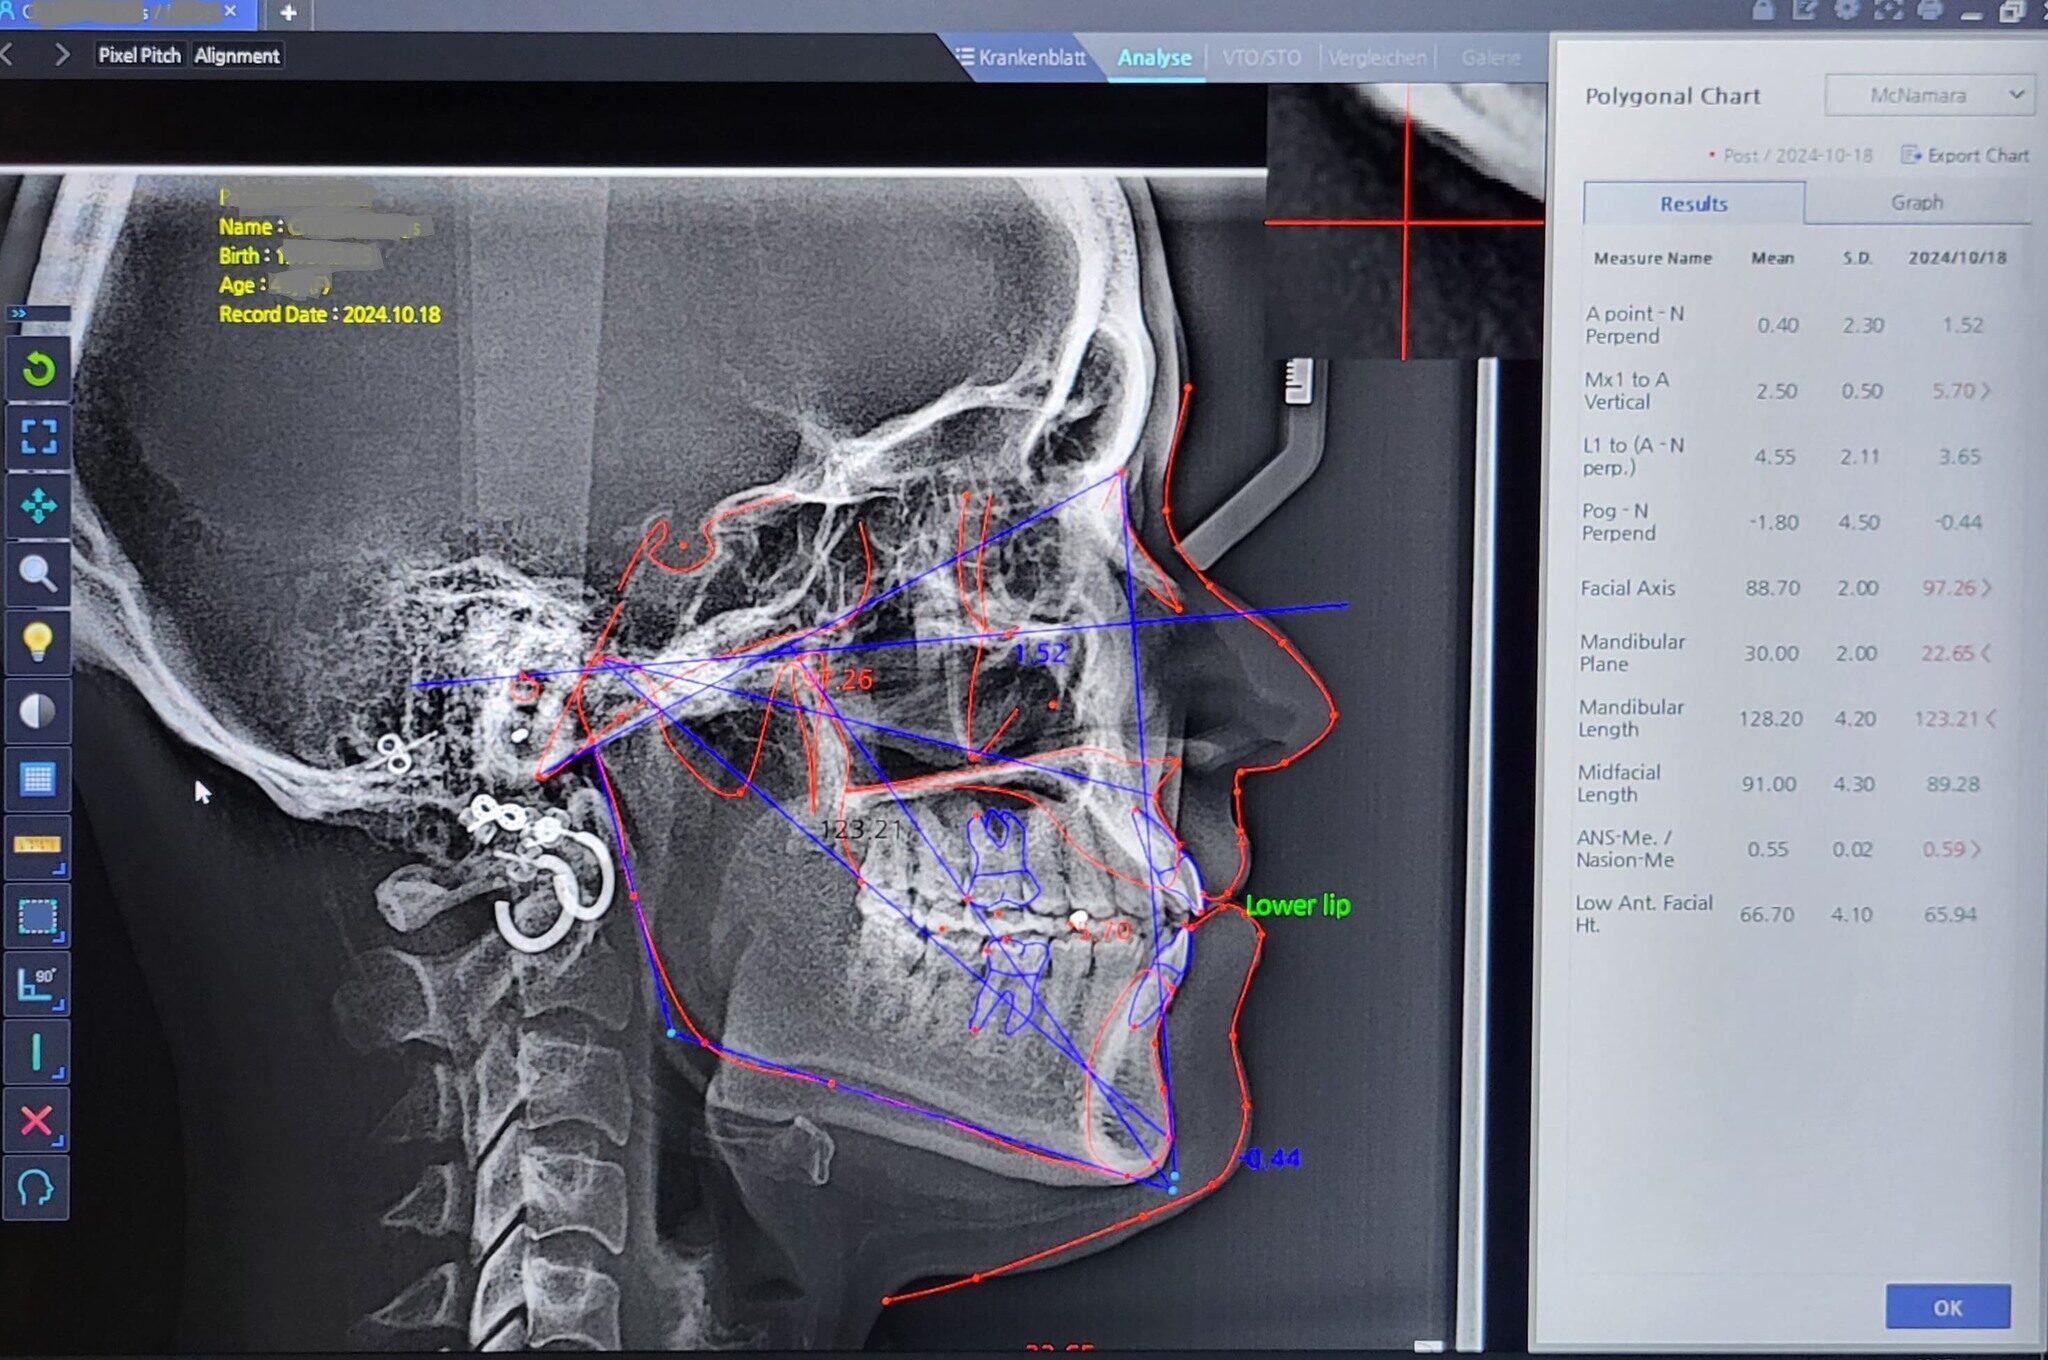

- Typ: OPG-FRS

HDX WILL DENTIO III FRS / 2 Sensoren

Panorama mit Ceph / 2 Sensoren

Ki gestützte Bildoptimierung für klare u.

scharfe Bildgebung